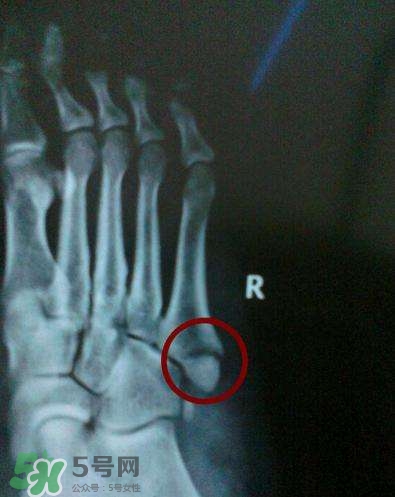

骨裂是骨折的一種,臨床上嚴(yán)格來(lái)說(shuō)沒(méi)有骨裂這個(gè)說(shuō)法, 骨裂只是普通的說(shuō)法,是骨折的輕微狀態(tài),也就是骨頭裂開(kāi)了,但是沒(méi)有移位,骨頭之間對(duì)位對(duì)線都是好的,所以一般不需要復(fù)位,只需要固定就可以,而骨折是一大類,包括沒(méi)有移位的骨折,也包括有移位的骨折。

一般骨裂分為移位骨裂和無(wú)移位骨裂、關(guān)節(jié)內(nèi)骨裂和關(guān)節(jié)外骨裂,一般骨裂4-6周軟骨愈合,3月以上骨性愈合,不愈合的很少見(jiàn),但是畸形愈合的較多見(jiàn)。但是這也不是絕對(duì)的,需要看骨裂的具體的部位損傷的程度。